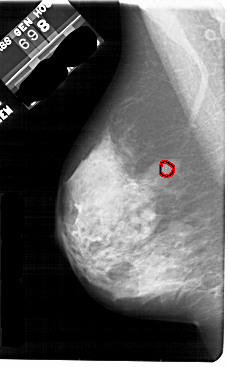

A_1844_1.RIGHT_CC

RIGHT_CC LINES 5251 PIXELS_PER_LINE 2971 BITS_PER_PIXEL 12 RESOLUTION 43.5 NON_OVERLAY